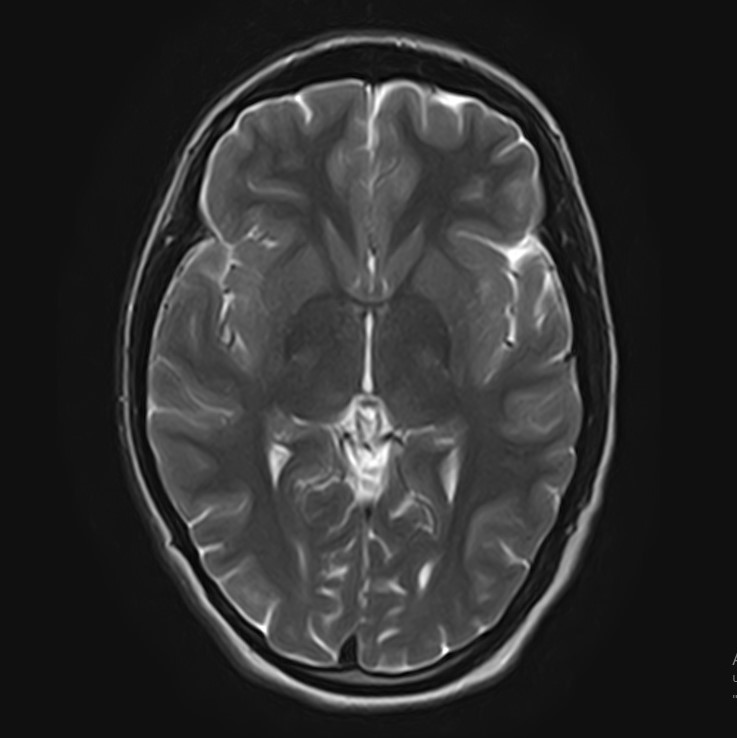

В клинике «Доступная медицина» можно пройти комплексное обследование, включающее в себя два протокола сканирования близко расположенных друг от друга анатомических областей – шейного отдела позвоночника и головного мозга.

Сканирование проводится на современном высокопольном магнитно-резонансном томографе закрытого типа TOSHIBA VANTAGE TITAN 1,5 Тесла, который делает послойные срезы в разных плоскостях с шагом от 1 мм и на основе полученных данных создает трехмерные изображения превосходного качества. Метод исследования позволяет в мельчайших подробностях визуализировать состояние всех структур головного мозга и шейного отдела позвоночника, что дает возможность выявлять патологические изменения на ранних стадиях и назначать своевременное лечение.